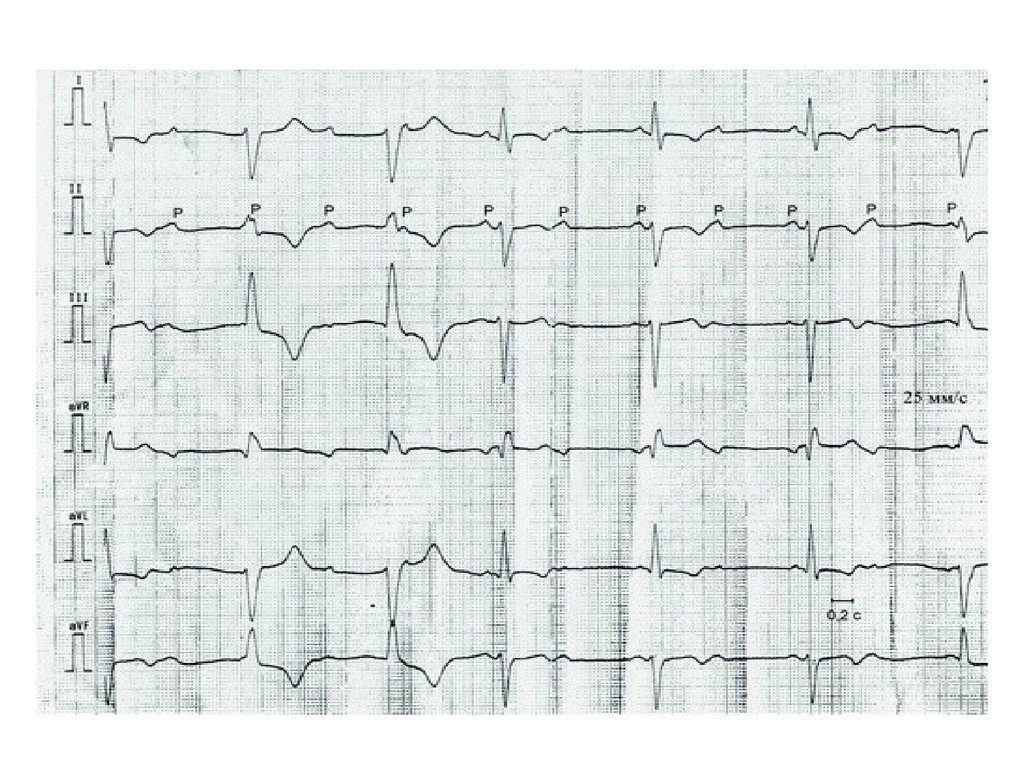

Нарушение проводимости.

АВ-блокада

АВ-блокада 2 ст.

• Тип Мобитц 1. Прогрессирующее

удлинение PQ-интервала с последующим

выпадением QRST(самый длинный PQ

перед паузой)

• Тип Мобитц 2. Постоянный нормальный

или удлиненный PQ > 0,22 с без его

прогрессирующего удлинения.